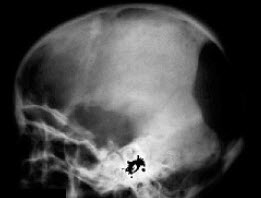

5、单项选择题 头颅凹陷性骨折,应首选哪种投照体位()

A.切线位

B.头颅侧位

C.汤氏位

D.颅底位

E.头颅后前位

E.左心缘旁区

140、单项选择题

男,6岁,尿量明显增多伴眼球突出1年,结合图像作出最可能的诊断()

A.骨髓瘤

B.转移瘤

C.白血病

D.淋巴瘤

E.Langerhans组织细胞增生症